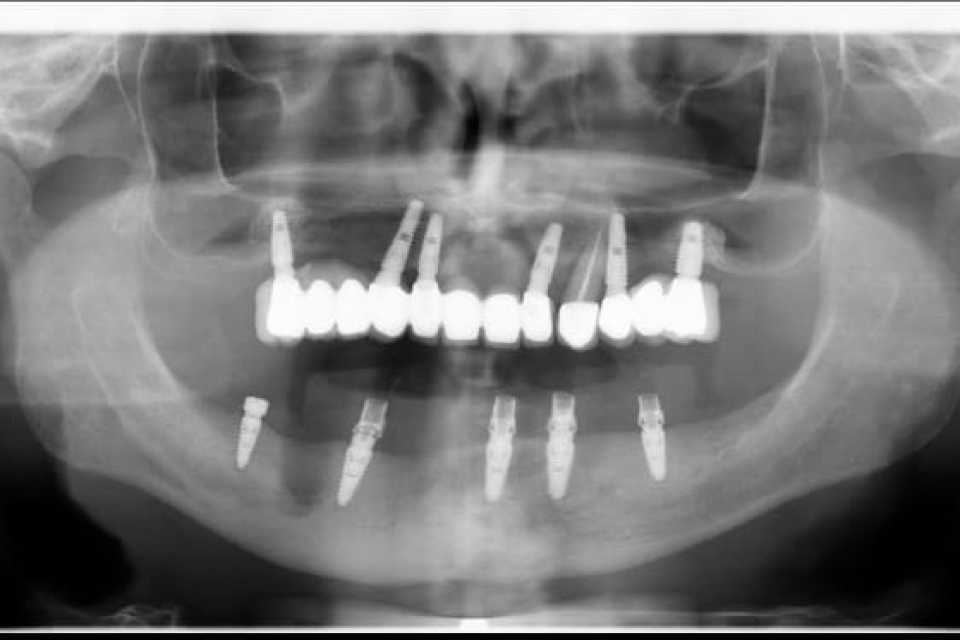

Pacientul în vârstă de 55 de ani, s-a prezentat în cabinet cu o lucrare dentara metalo ceramica ,la nivelul mandibulei, de 9 elemente pe 4 dinti parodontotici irecuperabil.

Împreună cu pacientul am hotărât inserarea a 5 implanturi dentare Mega Gen Anyridge, cu ajutorul cărora într-o prima fază am protezat a doua a zi cu o lucrare provizorie, astfel încât la 2 luni de la intervenție să realizăm lucrarea finală de 12 elemente ceramica pe zirconiu.